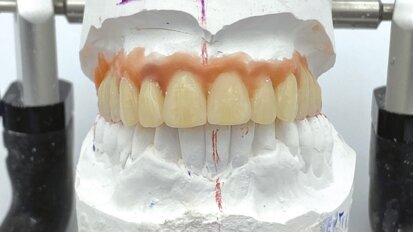

F22 Young, un dispositivo estetico funzionale per il trattamento dei pazienti in crescita con malocclusione di classe II: Case Report

La classe II scheletrica rappresenta una malocclusione molto diffusa nella popolazione e può presentarsi con un’ampia varietà di configurazioni dentali ...